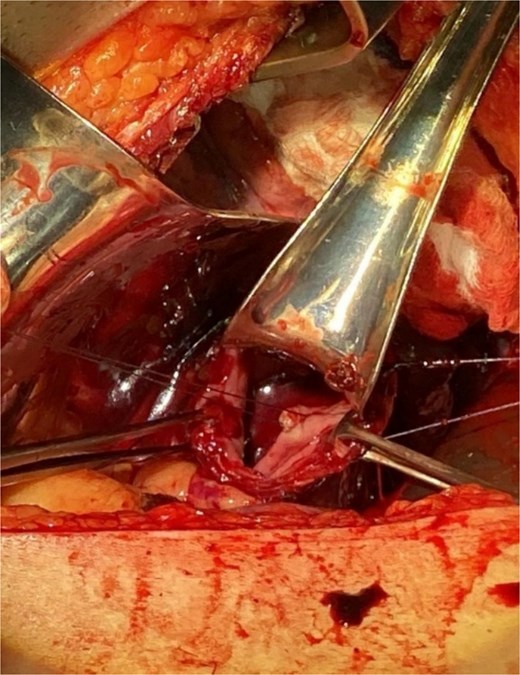

A 46-year-old male with a history of achalasia, for which he had undergone Heller myotomy with Nissen fundoplication in 2015, presented to the emergency department with a 2-day history of weakness and hematemesis. On admission, laboratory investigations revealed a significant drop in hemoglobin to 5 g/dl. Vital signs demonstrated tachycardia (122 beats per minute) and hypotension (70/50 mmHg), consistent with hemorrhagic shock. Initial management included aggressive resuscitation. Emergent gastroscopy was performed, which revealed the stomach filled with blood but failed to identify a clear bleeding source (Fig. 1). The patient remained hemodynamically unstable, necessitating transfusion of additional blood products. A computed tomography angiography was subsequently performed, revealing a markedly dilated, sigmoid-shaped esophagus, likely a sequela of end-stage achalasia. Furthermore, a contrast blush in the region of the distal esophagus, consistent with active ongoing bleeding (Fig. 2). An initial attempt was made to control the bleeding through angioembolization; however, this attempt was unsuccessful.

Demonstrates the gastroscopy findings, showing the stomach filled with blood.